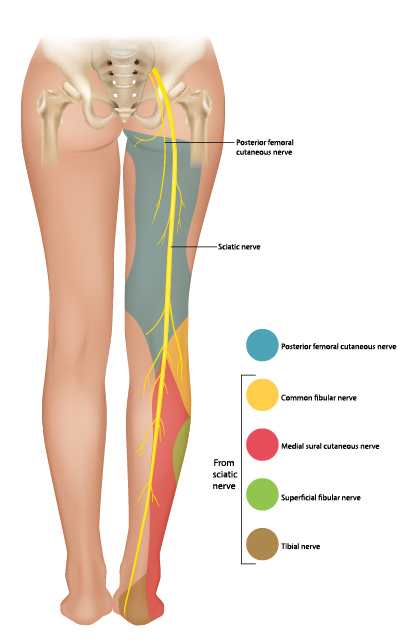

sacral plexus

Serves the buttock, lower limb, pelvic structures, and perineum

sciatic nerve

S1-S3

femoral nerve

L2-L4